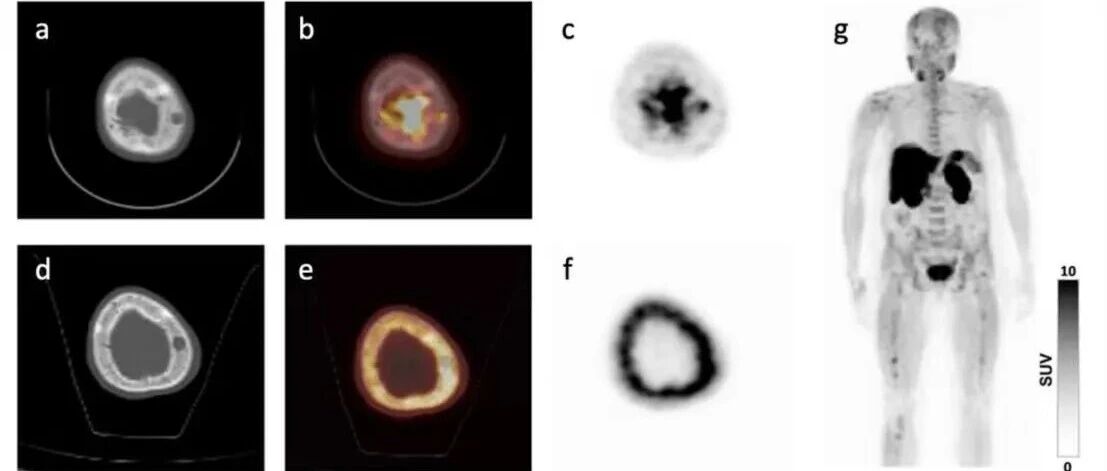

这种皮肤肿瘤竟比肺癌更会 "潜伏"?FDG PET/CT “一网打尽”